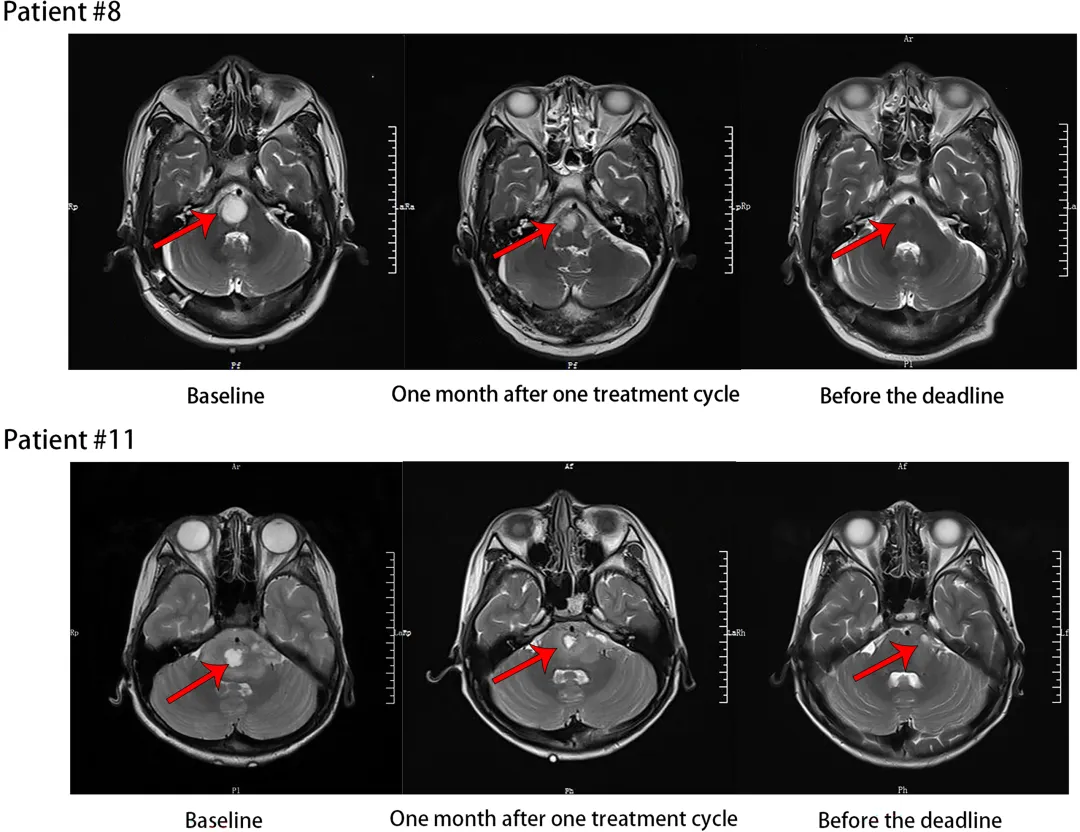

这项发表于《International Journal of Cancer》的研究,首次在全球探索了声动力疗法联合放疗用于脑干胶质瘤(含高级别)的安全性。核心结论:非常安全。所有11名患者治疗相关的不良反应均为1-2级(轻度至中度),未出现任何3级及以上严重不良反应或剂量限制性毒性。治疗耐受性良好。疗效信号:在可评估的患者中,72.7%的患者病情保持稳定,18.2%达到部分缓解(肿瘤缩小)。研究通过MRI影像直观地展现了肿瘤治疗后的变化。例如,患者#8和患者#11在基线期、治疗周期结束后1个月以及随访截止前的MRI对比显示,肿瘤得到了有效控制或缩小。

图3. 上图展示了两位患者治疗前后MRI的对比变化。患者的中位无进展生存期(PFS)达到 9.2个月,中位总生存期(OS)为 11.7个月,为后续研究奠定了坚实的基础。